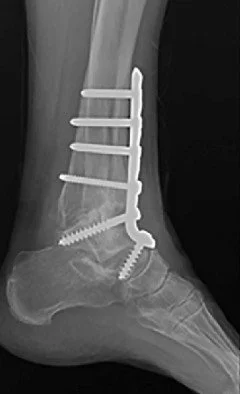

Anterior ankle fusion approach

For more complex alignment issues, an anterior approach allows thorough preparation and the addition of a low profile anterior plate to crossing screws for added stiffness. Case series and technique papers report high union rates, often in the ninety to ninety six percent range.²⁶ ²⁷ European Review . This is my fusion approach of choice for most patients due to the high success rate

anterior ankle fusion with anterior ankle arthrodesis plate